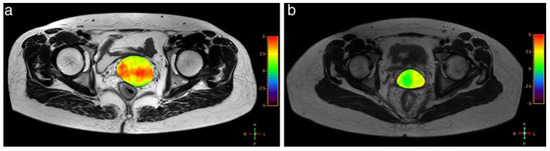

- Takayama, Y.; Nishie, A.; Sugimoto, M.; Togao, O.; Asayama, Y.; Ishigami, K.; Ushijima, Y.; Okamoto, D.; Fujita, N.; Yokomizo, A.; et al. Amide proton transfer (APT) magnetic resonance imaging of prostate cancer: Comparison with Gleason scores. Magma Magn. Reson. Mater. Phys. Biol. Med. 2016, 29, 671–679. [Google Scholar] [CrossRef]

- Jia, G.; Abaza, R.; Williams, J.D.; Zynger, D.L.; Zhou, J.; Shah, Z.; Patel, M.; Sammet, S.; Wei, L.; Bahnson, R.R.; et al. Amide proton transfer MR imaging of prostate cancer: A preliminary study. J. Magn. Reson. Imaging 2011, 33, 647–654. [Google Scholar] [CrossRef] [Green Version]